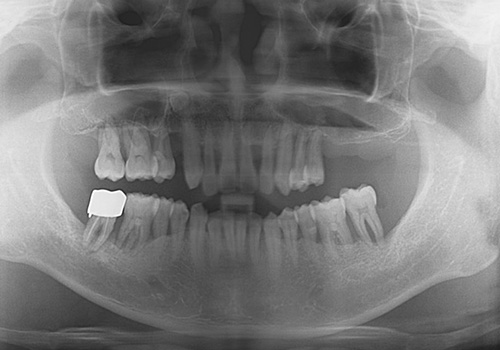

김○인님 임플란트 식립 전

2019년 7월

김○인님 임플란트 식립 후

2022년 8월 -